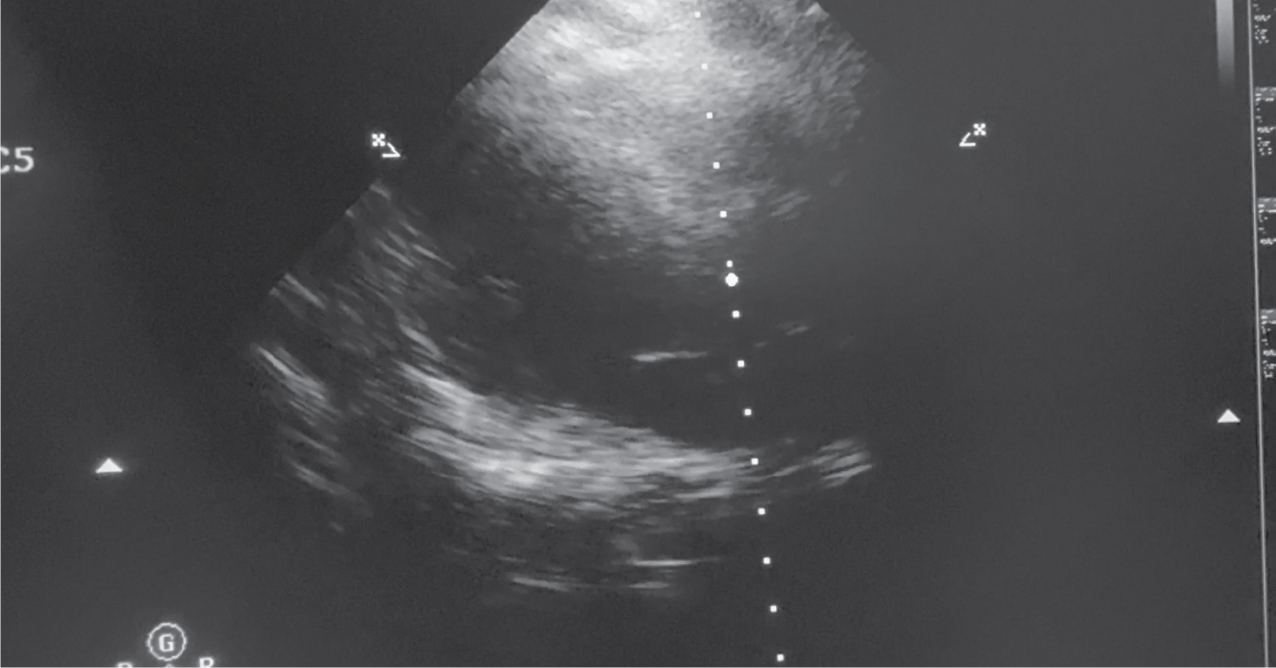

Surgical resection of the tumor, including the fossa ovalis attachment, was performed and sent for histopathological examination. This approach minimizes the risk of recurrence. Postoperative echocardiography confirmed the absence of residual tumor mass

in the left atrium (Fig. 4).

Figure 4. Postoperative Echo showing absence of the tumor in the left atrium.